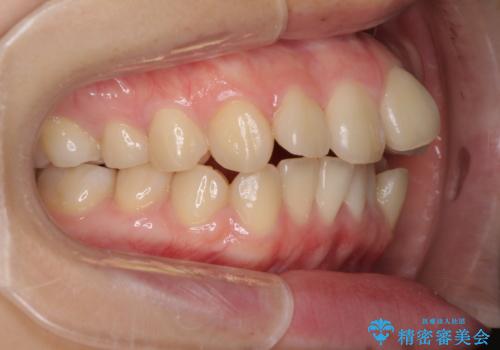

- デコボコと飛び出した前歯を治したいとのことで来院された患者様です。

ゴムかけを活用して上顎歯列全体を後方移動し、IPR(歯と歯の間を削る)によってデコボコが解消するように設計し、インビザラインにより治療を行うこととしました。

後方移動に際し、上下顎の親知らずは4本とも抜歯することとしました。

毎日しっかりと装着してくださったので、概ねシミュレーション通りに歯を移動させることができました。

治療前には接触することのなかった上下の前歯が接触するようになり、食事の際前歯でものをかみ切れるようになりました。

気にしていた口元の印象が改善され、患者様には大変満足していただきました。